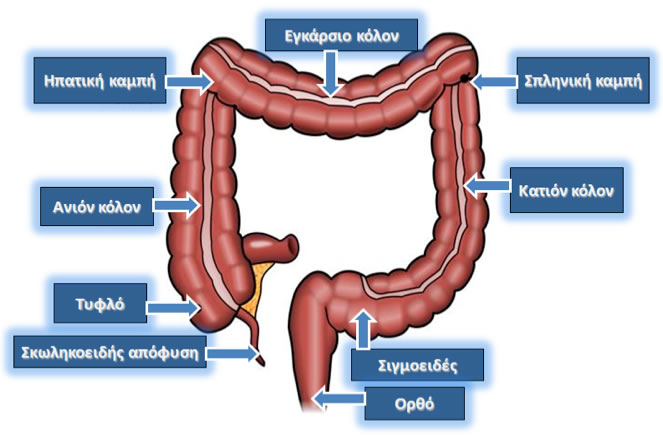

Το παχύ έντερο και ο πρωκτός αποτελούν τα τελευταία τμήματα του πεπτικού σωλήνα. Το παχύ έντερο, που μοιάζει με ένα μακρύ σωλήνα μήκους 1,5 μέτρων, διαιρείται στο κόλον που έχει σχήμα Π και το ορθό, το οποίο αποτελεί την αποθήκη των κοπράνων, πριν αυτά αποβληθούν από τον οργανισμό μέσα από τον πρωκτό. Υπολείμματα τροφής, που έχουν υποβληθεί στη διαδικασία της πέψης και της απορρόφησης θρεπτικών συστατικών από το λεπτό έντερο, εισέρχονται στο κόλον. Το κόλον απομακρύνει νερό και ηλεκτρολύτες από τα υπολείμματα της τροφής, τα οποία λαμβάνουν στερεά μορφή και αποβάλλονται από τον οργανισμό κατά την αφόδευση με την μορφή κοπράνων μέσα από το άνοιγμα του πρωκτού.

Το παχύ έντερο

(Τροποποιημένο από: https://www.fascrs.org)